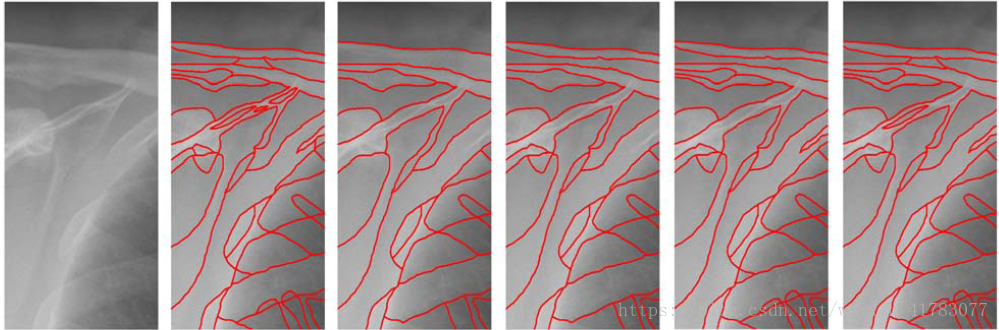

文献[34]提出了一种使用卷积神经网络实现在X射线图像中骨骼结构分割的方法,文献采用四种卷积神经网络模型提取图像特征,四种不同配置如表1所示,并在最后一层用softmax分类器对像素进行二分类,将骨骼区域从周围组织中分割出来。由于X射线图像的分辨率很高,为了减少训练的时间,选取局部感兴趣的区域进行训练。在分割的过程中,再不需要人为干涉,避免了人为选取特征存在误操作的风险。骨骼分割结果如图12所示,实验结果表明,第四种神经网络模型在像素误差(Pixel error)、兰德误差(Rand error)和分裂合并翘曲误差(Warping error)三个指标上均取得了优良的性能,如表2所示。

图12 四种卷积神经网络模型下的骨骼轮廓提取结果。从左到右依次为:原图像,模型1,模型2,模型3,模型4